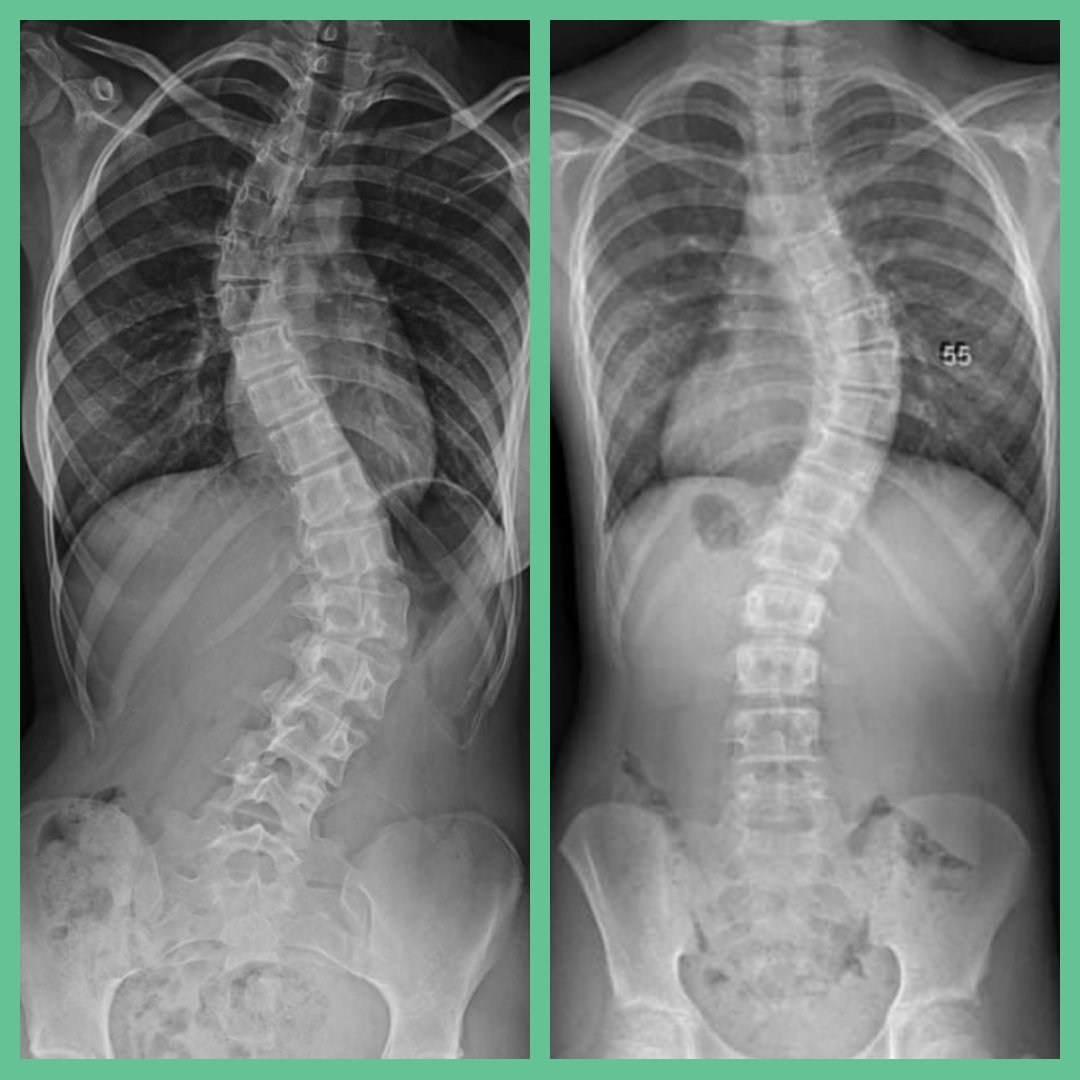

ف إنحناء العمود الفقري هو عبارة عن تشوه بحصل للعمود الفقري في شكل انحناء جانبي

غالبية الحالات بتكون بسيطة لكن احيانا بزداد التشوه مع النمو

#أنواعه

- C Shape

- S Shape